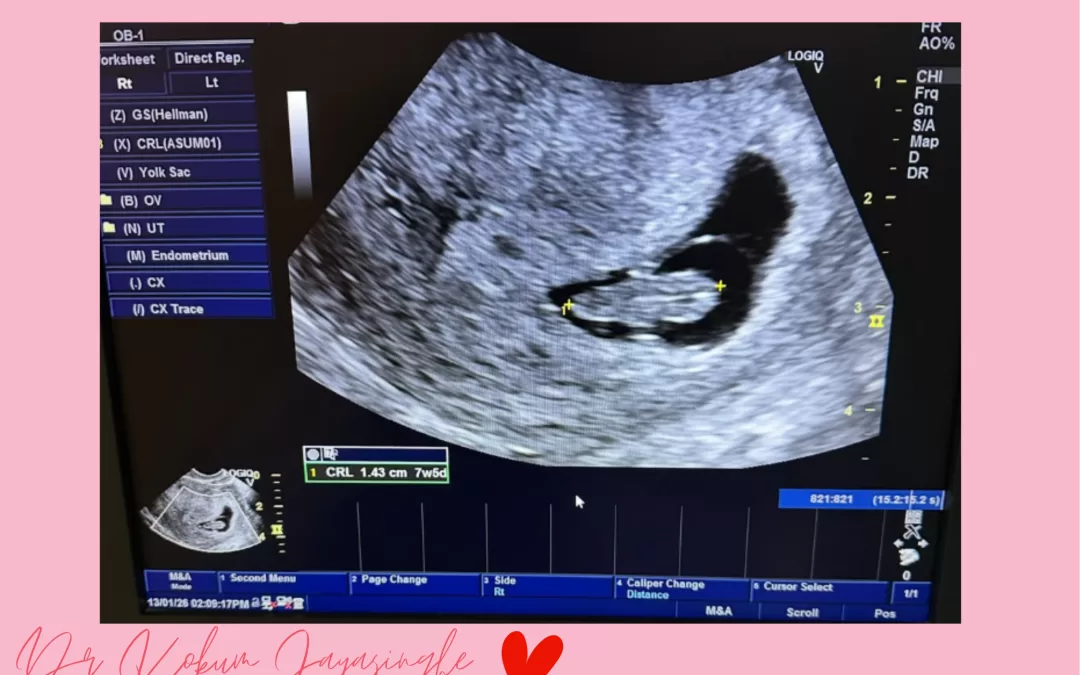

And then today, I finally met them in person scan after scan, heartbeat after heartbeat.

One woman broke down the moment her baby’s heart appeared on the screen.

In that small scan room, it wasn’t just an ultrasound.